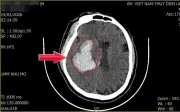

Ông Dương, 51 tuổi ở Trung Quốc, tử vong sau 3 ngày cấp cứu do thói quen ăn uống không khoa học như lẩu, thịt nướng, hải sản vào đêm khuya. Bác sĩ cảnh báo về nguy cơ từ đồ ăn nhiều đường, mặn, chất béo.